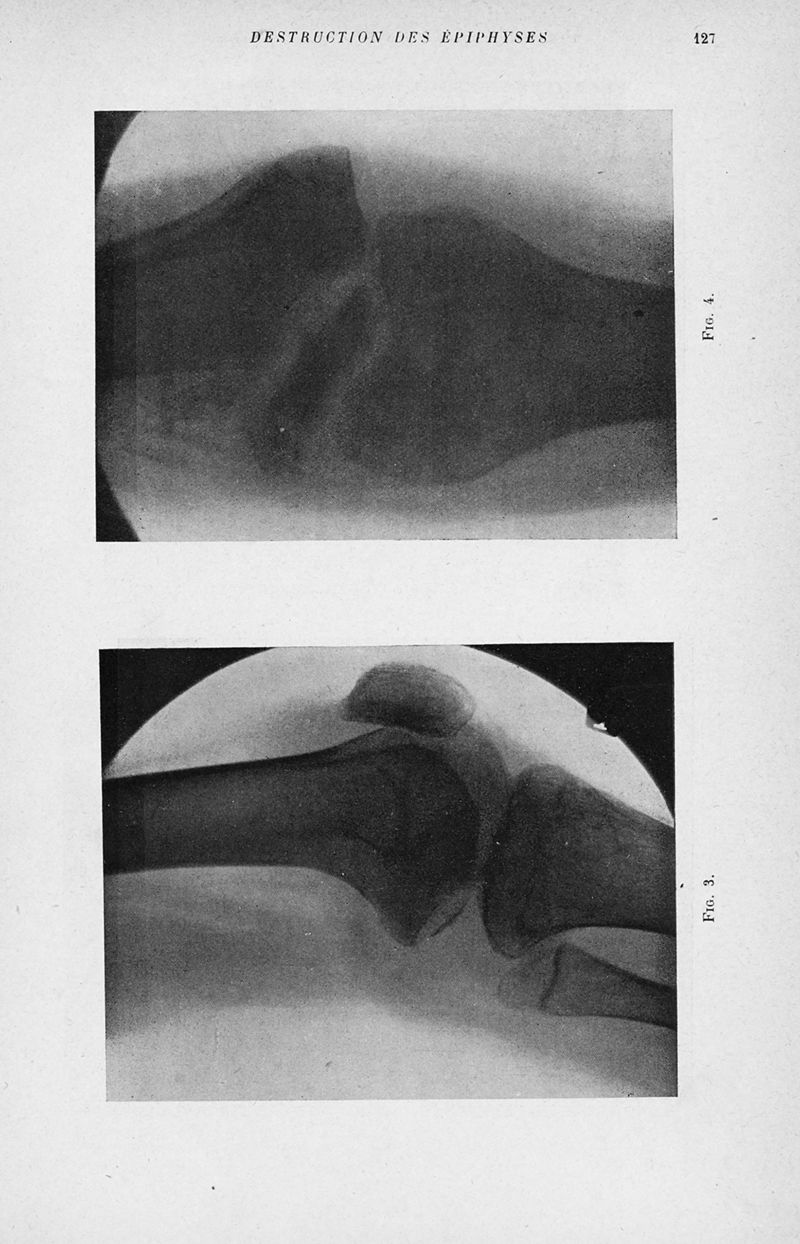

Bulletins et mémoires de la société nationale de chirurgie

Tome LI, 1925. - Paris : Masson, 1925.